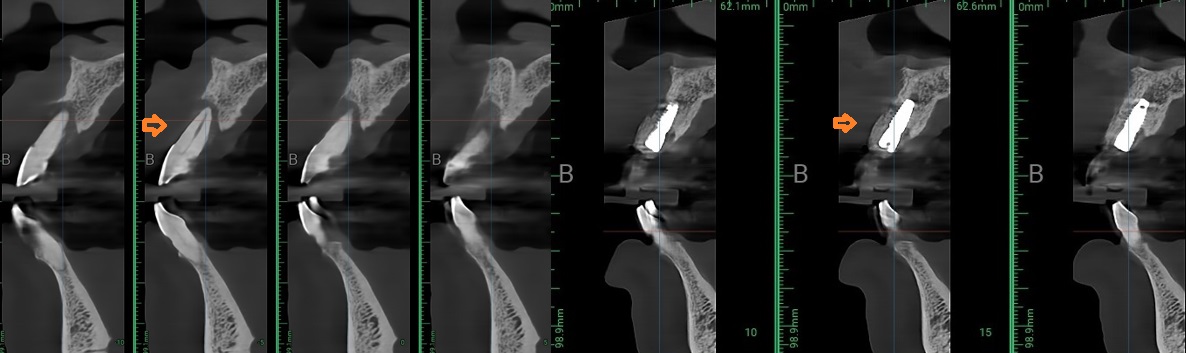

안면 골격을 다루는

구강악안면외과 전문의 경험으로

짧은 시간에도 정밀한 식립을 완성합니다.